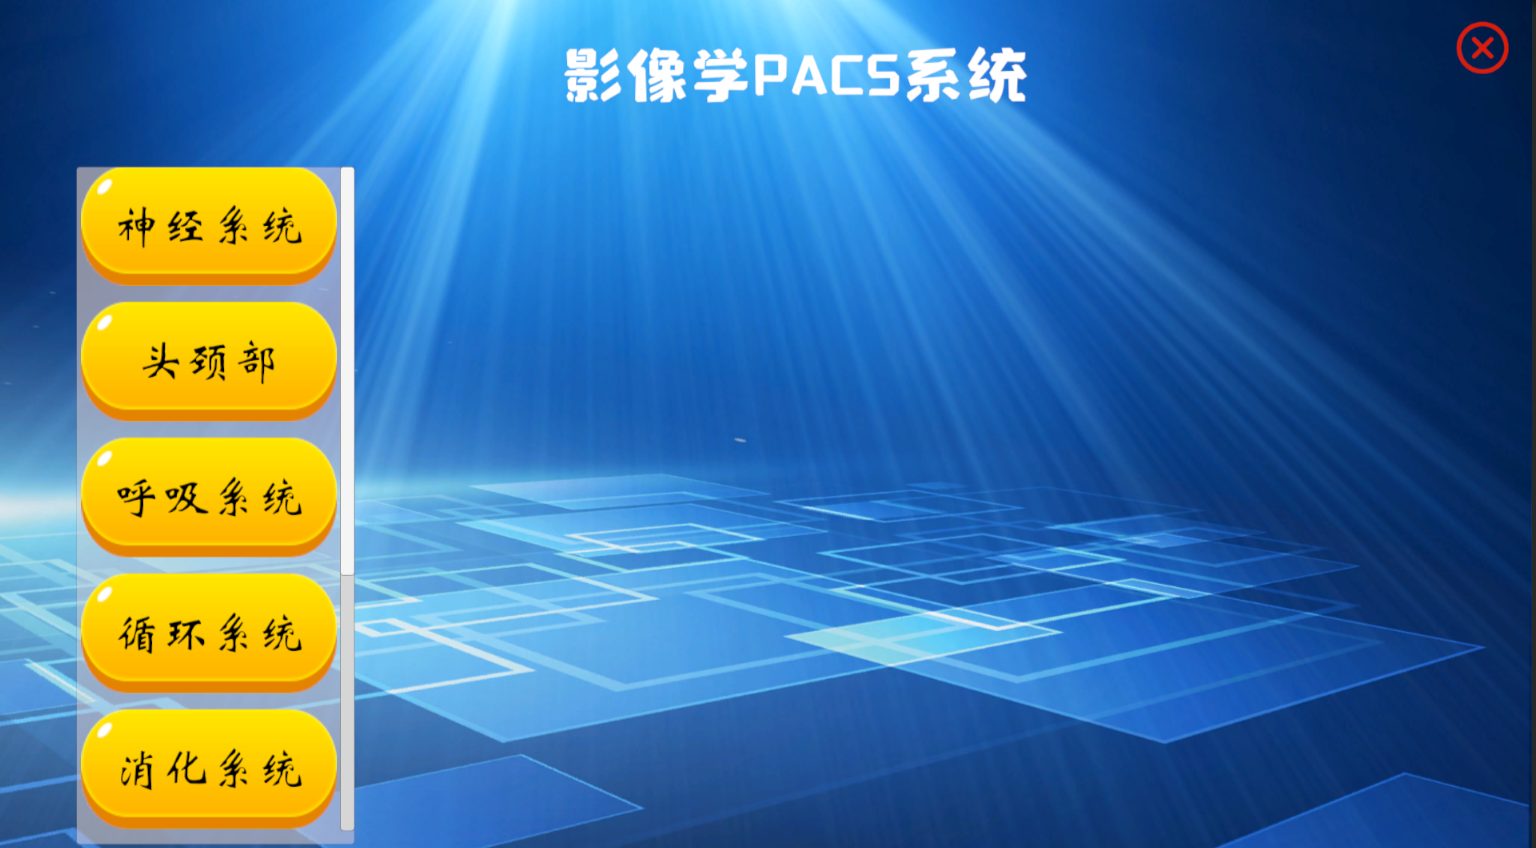

虚拟教学+虚拟介入手术+影像学PACS+沉浸式第一人称开放世界探索

本产品打破以往产品功能单一的局面,目前具有解剖教学、组胚教学、影像教学、模拟介入手术等功能

影像学模块模拟PAC系统,在这里您可以学习到各种疾病的影像学表现